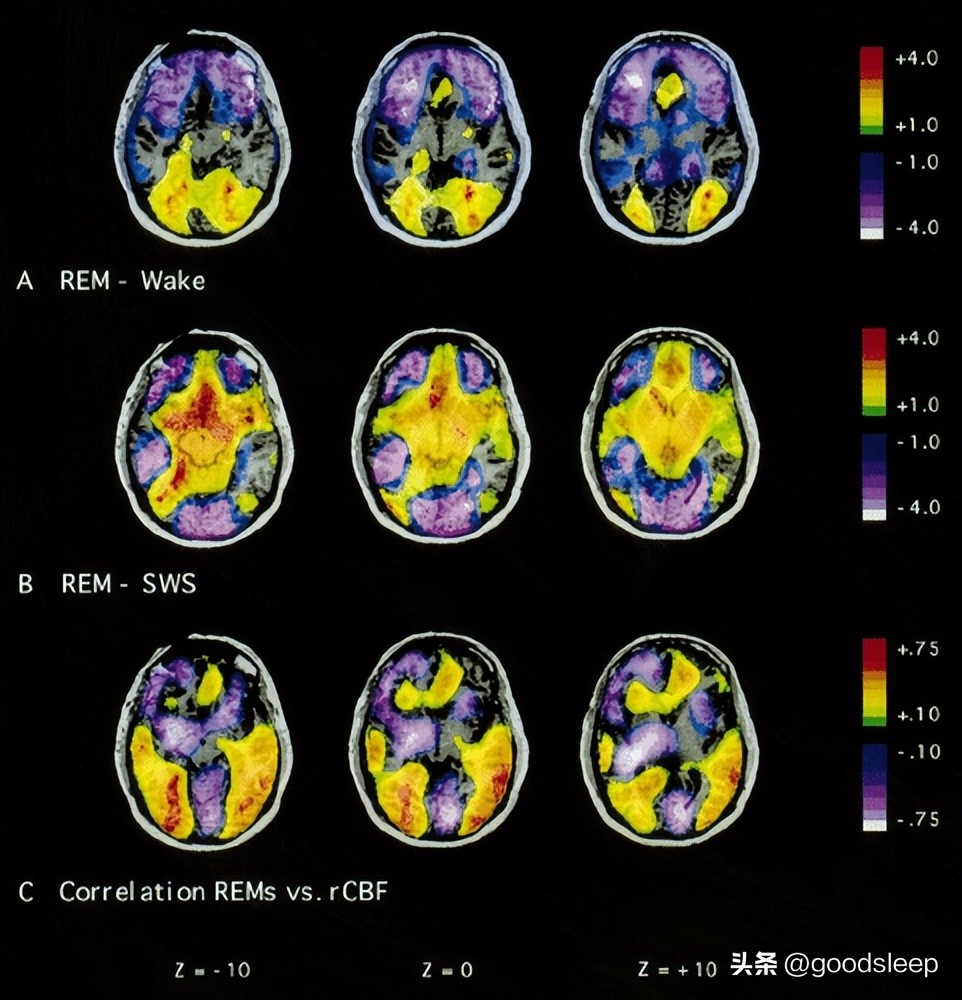

这种现象叫做「睡眠麻痹(Sleep paralysis)」,属于睡眠疾患中的异睡症(Parasomnia),是一种在清醒和快速动眼睡眠期(rapid eye movement,REM)之间的过渡期所发生的异常现象。在快速动眼睡眠期,我们会不断地作梦,但大脑为了避免我们做梦时将梦境「演」出来而伤害到自己,因此在这个时期大脑会暂时麻痹我们的身体,让肌肉失去张力。所以鬼压床的现象就是我们在失去肌肉张力的这段时间清醒,导致我们感受到这种无法动弹但意识清楚的现象。

那问题来了,为什么会看到「鬼影」呢?研究结果发现,这些画面其实是我们大脑自己产生的。在REM期我们正处于肌肉失去张力无法活动的状况,但是我们的意识是清醒的。若大脑发出信号要进行肢体的活动时,但我们的身体因为处于肌肉失去张力的状况无法完成大脑指令,这种不一致的状况会让大脑感到困惑。这种困惑感会影响大脑建构我们的自我意识或身体形象,大脑会为了消除这种困惑而自己建构了我们的身体形象。

第一,REM期前脑区域反应较迟钝。前脑中有帮助我们区分自己和他人的神经元,这个神经元在清醒的状态下会被前脑区域的回馈机制所控制,但在REM期前脑反应迟钝难以抑制这个神经元,导致这个神经元过度活化,难以区分我们大脑自动填补的产物是自我还是他人。

第三,神经化学的作用下,大脑会为这些鬼故事创造合适的环境。在REM期清醒的状态下,大量的血清素会充斥着我们的大脑,这会刺激我们脑中血清素2a受主,在这种状况下会引发我们经验到一些「神秘经验」,会让我们将毫无意义的信息赋予新的意义。